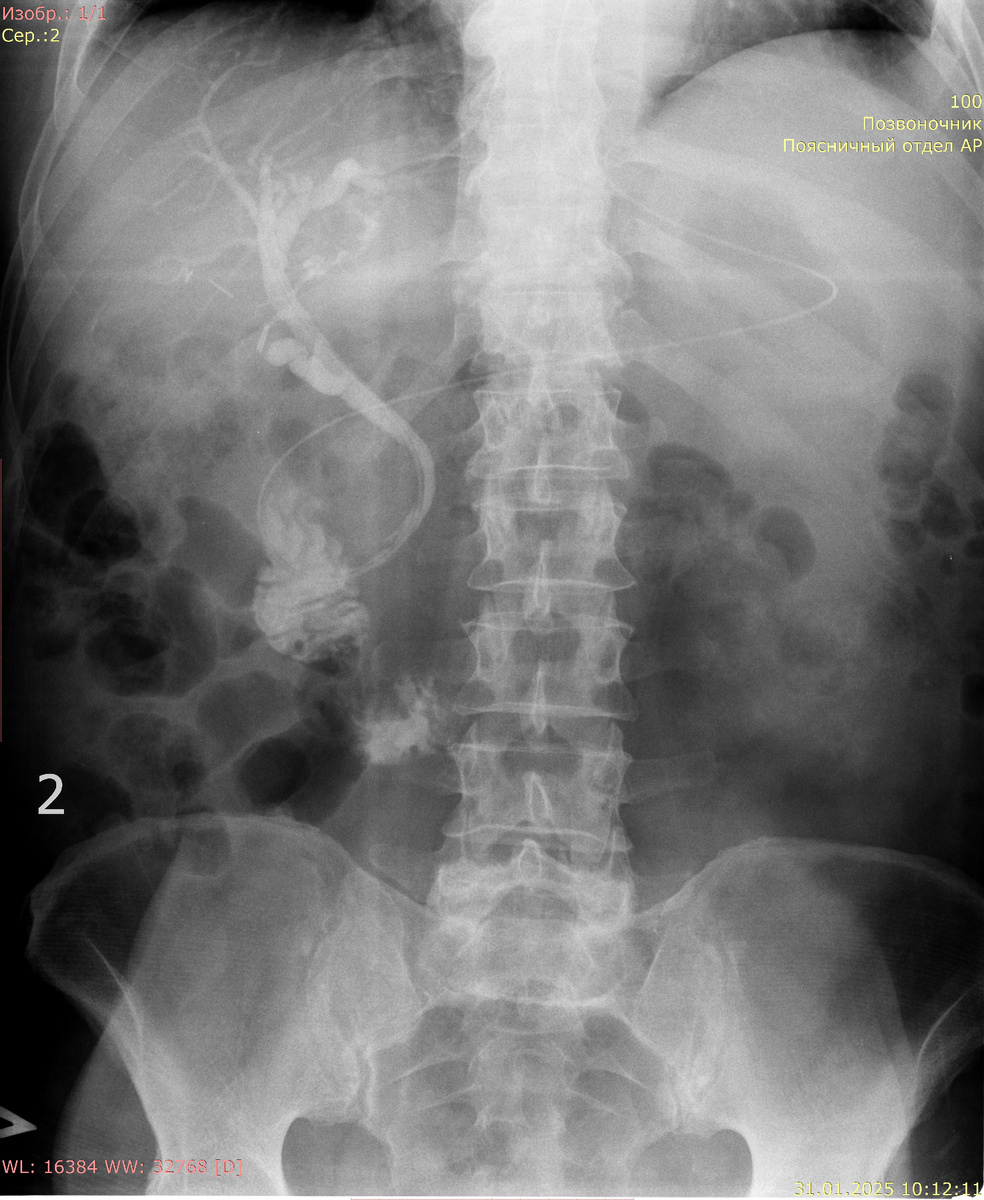

НБД (назобилиарное дренирование) — это медицинская процедура, которая используется для обеспечения оттока желчи и других жидкостей из печени или желчного пузыря. Обычно она применяется в случаях, когда естественный отток затруднён по причинам, таким как желчнокаменная болезнь, опухоли, воспалительные процессы или после хирургических вмешательств. Контрастом выполнились внутри- и внепеченочные протоки. Диаметр холедоха около 6 мм, дефектов не обнаружено. Тени металлических клипс в проекции пузырного протока. Контраст поступает в ДПК.

Заключение: состояние после холецистэктомии. Дефектов не обнаружено.